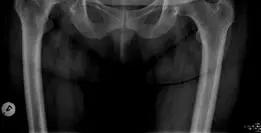

صورة توضيحية لـ مفصل الورك الصناعي غير المثبت: دليل شامل لمرضى صنعاء مع الأستاذ الدكتور محمد هطيف

صورة طبية: مفصل الورك الصناعي غير المثبت: دليل شامل لمرضى صنعاء مع الأستاذ الدكتور محمد هطيف